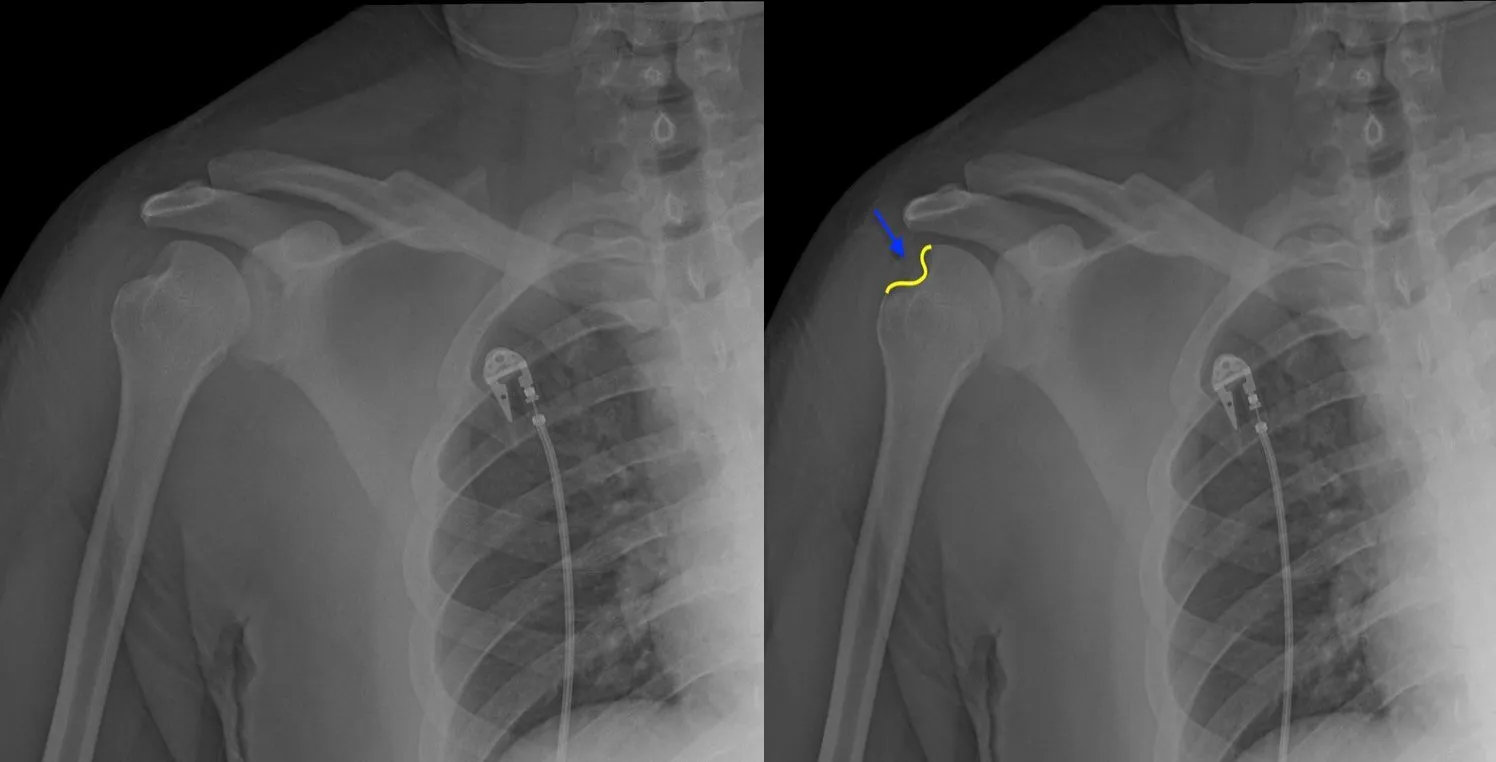

Recurrent Shoulder Dislocation

Bankart Lesion

Rotator Cuff Tear